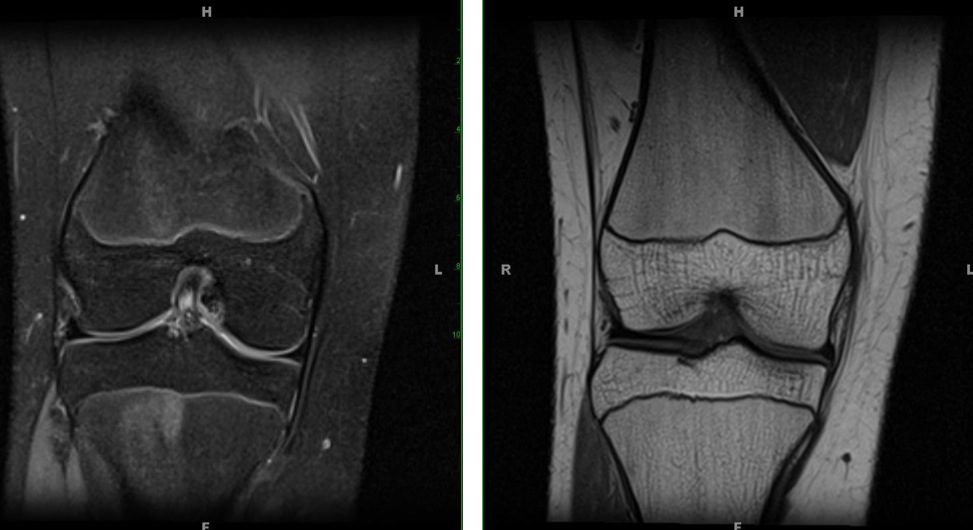

Figure 1 for case Mild alta and early mucoid ACL

Figure 1

Figure 2 for case Mild alta and early mucoid ACL

Figure 2